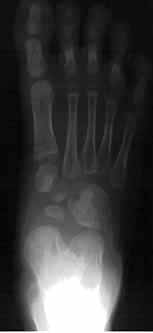

この疾患の構造は、内反足の逆と考えると理解しやすいと思います。簡単に言うと、内反足は、距骨に対しその周囲の骨群が内方かつ下方へ内旋しながらずれているのですが、外反扁平足では、距骨に対しその周囲の骨群は外方かつ上方へ外旋しながらずれています。下の写真は典型的な外反偏平足です。正常足であれば距骨頭(距骨の先端)の正面に舟状骨があるのですが、これが距骨頭の外側に位置をかえていることがわかります。また、側面像で足の骨のアーチが無くなり偏平になっています。

外反偏平足では、距骨とその周囲の骨群との間に不安定性があり、体重をかけると足の前方部分がグニャッとなって外に向いてしまいます。この時、足の内側が突出しますが、こと突出した部分は距骨の頭であり、靴を履いているとこの部分があたって痛みがでることがあります。不安定性がありますので、歩行の時の蹴り出しに力が入らず、走るのが遅く、長距離歩行では疲れやすくなります。